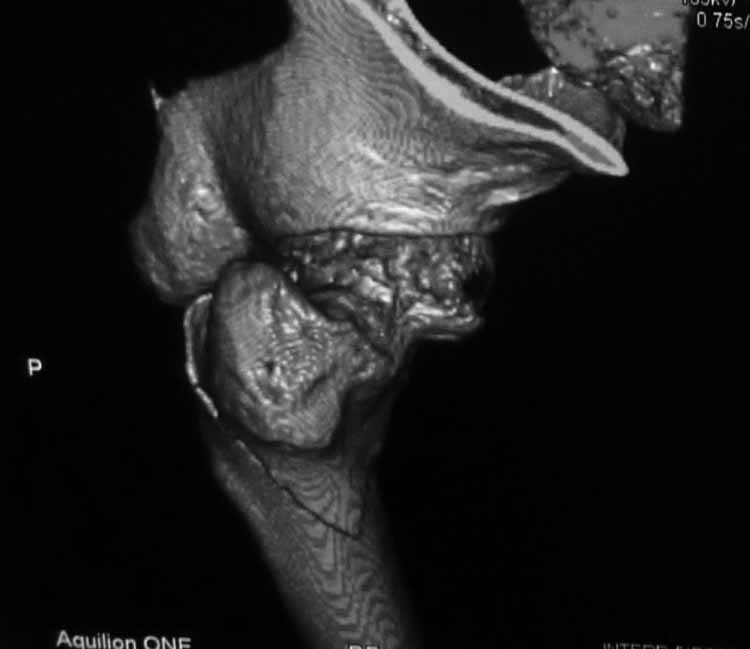

Пациентка 53 лет. ДТП 09.01.12: сочетанная травма: перелом 2-5 ребер справа, ушиб легких; перелом обеих лонных костей без смещения; закрытый перелом проксимального конца правой бедренной кости; открытый оскольчатый внутрисуставной перелом проксимальных концов костей правой голени.

В нашей клинике 11.01 выполнен минимально инвазивный остеосинтез большеберцовой кости (снимки до операции не перефотографировал) с пластикой перемещенными лоскутами дефекта, образовавшегося вследствие некроза кожи на передней поверхности голени. Бедро одномоментно делать не стал, не было уверенности в наличии перелома на уровне шейки. Во время операции смотрел тазобедренный сустав под ЭОПом, головка неподвижна. После операции повторили КТ, стало очевидно, что имеется субкапитальный перелом.

И еще: не явится ли препятствием для введения гвоздя дугообразный изгиб диафиза бедренной кости? Вершина деформации расположена на 110мм дистальнее проксимального края малого вертела. Это я по КТ измерил точно. Можно, конечно, думать о короткой ножке. Но обеспечит ли она достаточную фиксацию при таком переломе?